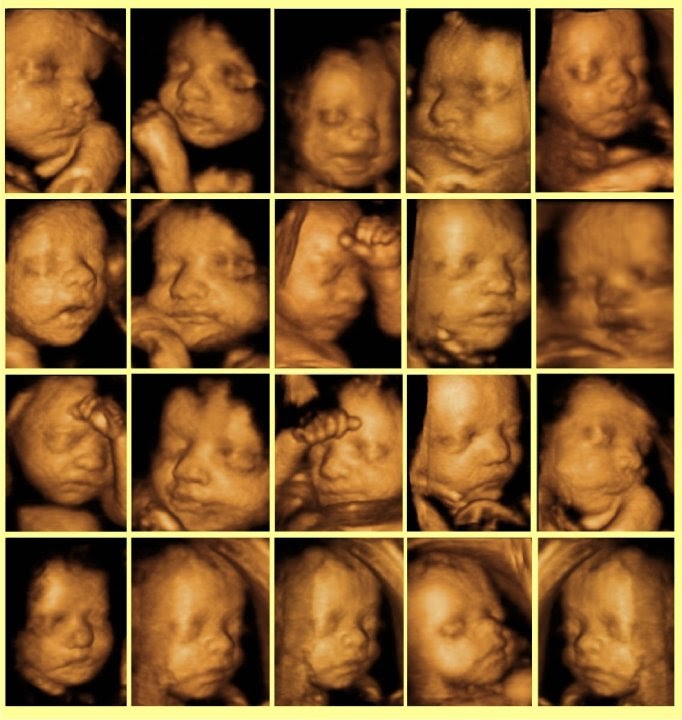

Günümüzde bebeğin oldukça detaylı bir şekilde görüntülenmesine yardımcı olan ultrason görüntüleme cihazlarından biri de 4 boyutlu ultrason cihazıdır. Bebeğin gerçeğe en yakın hali görüntülenmesine imkan sağlamaktadır.

4 boyutlu ultrason ile bebeğin gerçeğe yakın görüntüsü görülebilir. Bu yöntem ile bebeğin sağlıklı olup olmadığı, cinsiyeti ve kime benzediği bile rahatlıkla fark edilebilir. Klasik 2 boyutlu ultrason düz bir açıyla ayrıntısız görüntü verirken, 4 boyutlu ultrasonda her ayrıntı vardır.

- Ebeveynler bebeğin kime ve neye benzediğini çok merak ettikleri için 4 boyutlu ultrason sayesinde bebeğin ağzını, burnunu, yüzü ve çenesini, el ve ayaklarını net bir şekilde görebilmektedirler.